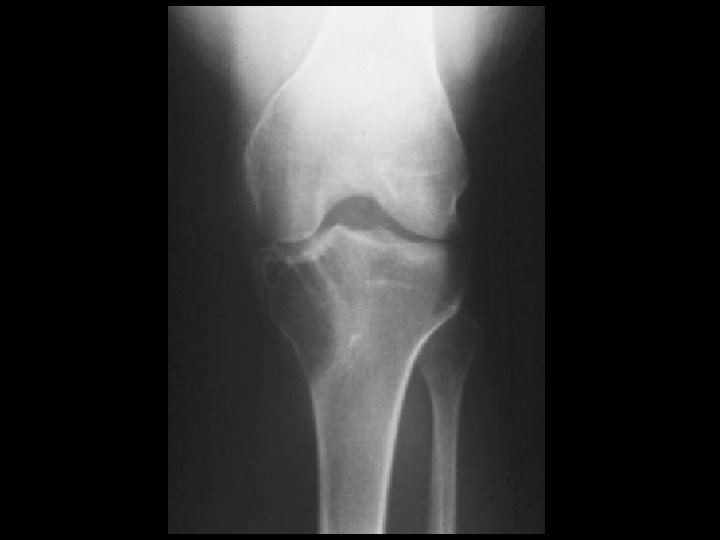

Aneurysmal bone cyst • Findings: – Eccentric metadiaphyseal lucent lesion with a thin sclerotic margin and fine internal septa • ddx: – Fibrous dysplasia – Chondromyxoid fibroma – GCT, chondroblastoma (if physis closed)